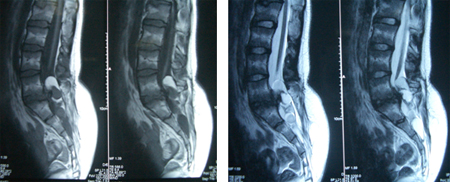

术后病理结果为成熟性囊性畸胎瘤。术后图片

术后:肢体活动和感觉正常,出现便秘、排尿稍困难,经康复训练后改善。